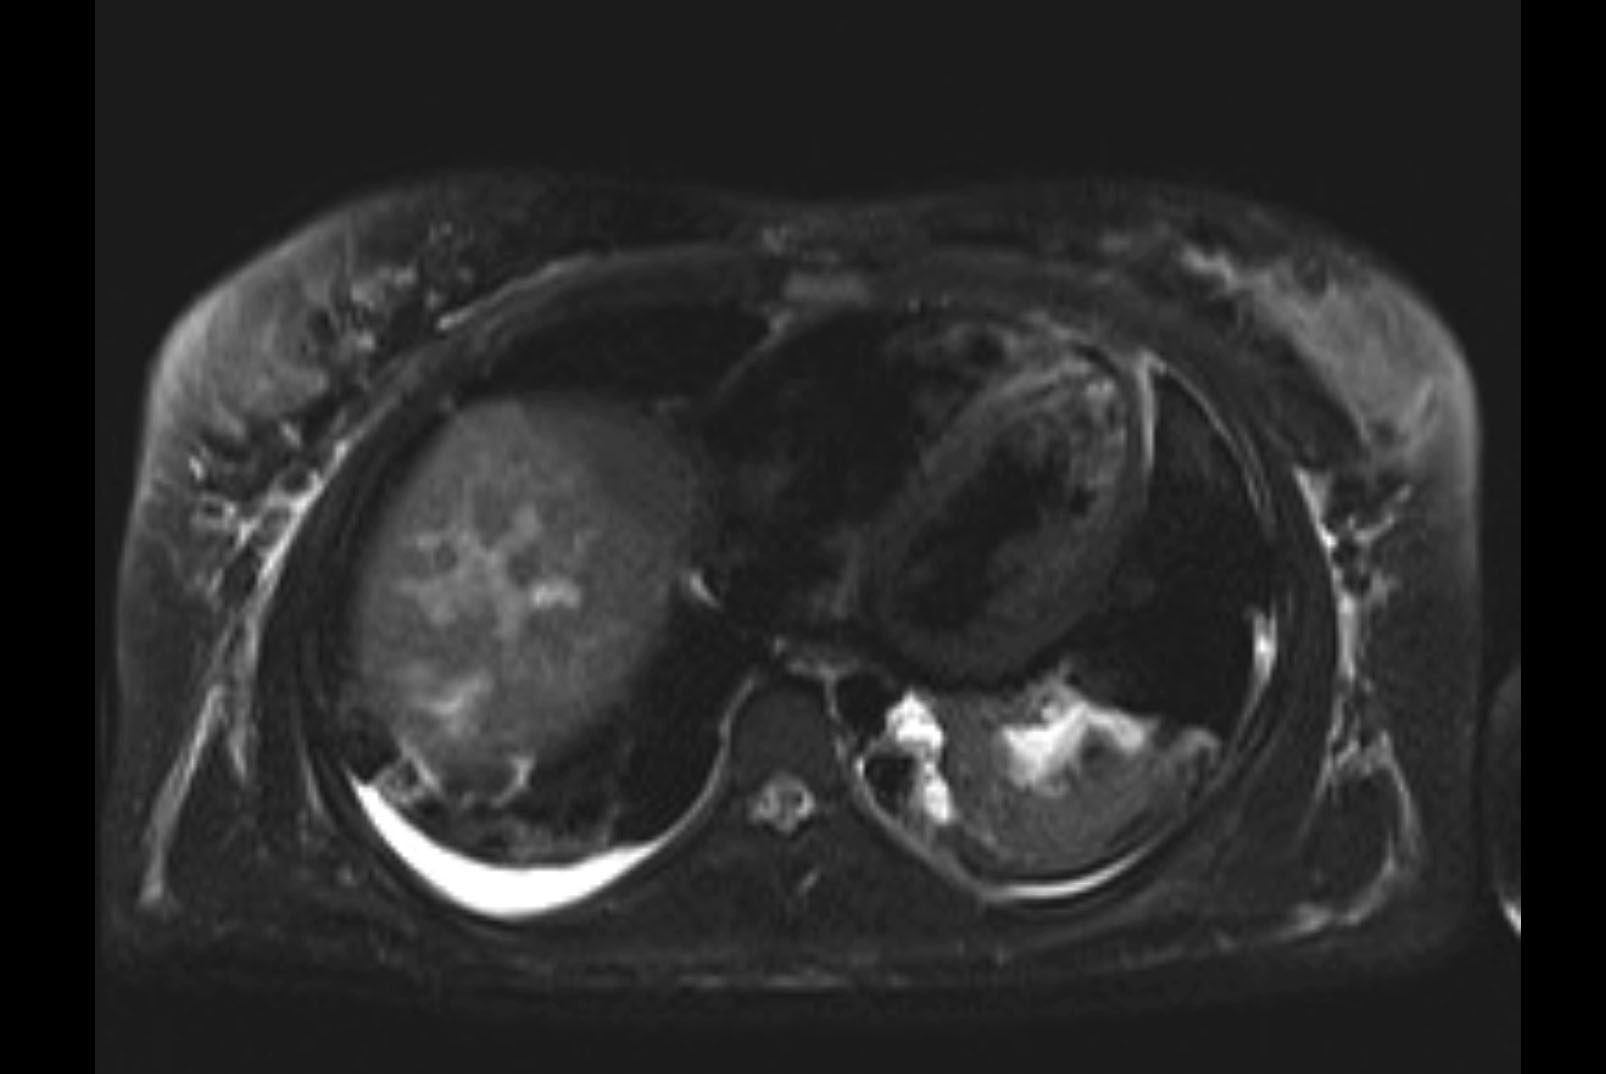

MRI T2